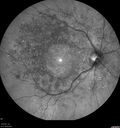

65 year old woman with gradually declining central vision. VA 20/200 in both eyes in the later photos (left eye was better in earlier photos). FAF shows pisciform tri-radiate lesions that are hyper FAF typical of stargardt's fundus flavimaculatus

Stargardt's Macular Dystrophy ABCA4 positivevaatamisi: 536 Fundus Autofluorescence shows central atrophy with Hyper FAF pisciform triradiate lesions. Images show some progression over 3 years of macular dystrophy.00000